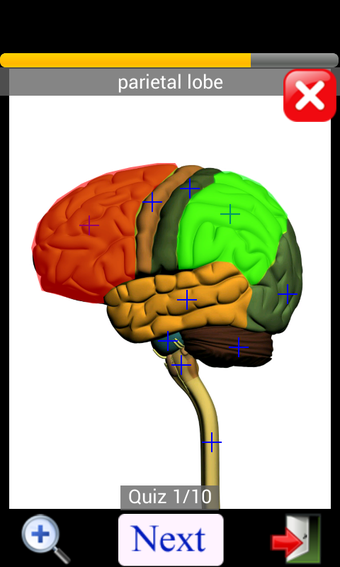

Anatomy Quiz Free es una aplicación de Android de Education Mobile que ofrece una amplia gama de cuestionarios para ayudar a los usuarios a aprender anatomía humana. La aplicación cuenta con más de 500 cuestionarios que ponen a prueba tu capacidad para identificar la ubicación correcta de un objeto dado su nombre. Los cuestionarios se generan a partir de modelos de anatomía 3D virtuales, lo que los hace más atractivos e interactivos. La aplicación es gratuita y no hay versiones premium ni compras dentro de la aplicación.

La aplicación es compatible con los idiomas inglés, francés, español y alemán, lo que la hace accesible para usuarios de diferentes partes del mundo. Las imágenes de alta resolución son nítidas y claras, y la función de zoom con pellizco te permite acercar y alejar las imágenes para una mejor vista. El cuestionario de posición viene con un temporizador, lo que lo hace más desafiante y emocionante. Además, la aplicación tiene una función de transferencia a la tarjeta SD, lo que facilita su transferencia a otros dispositivos.